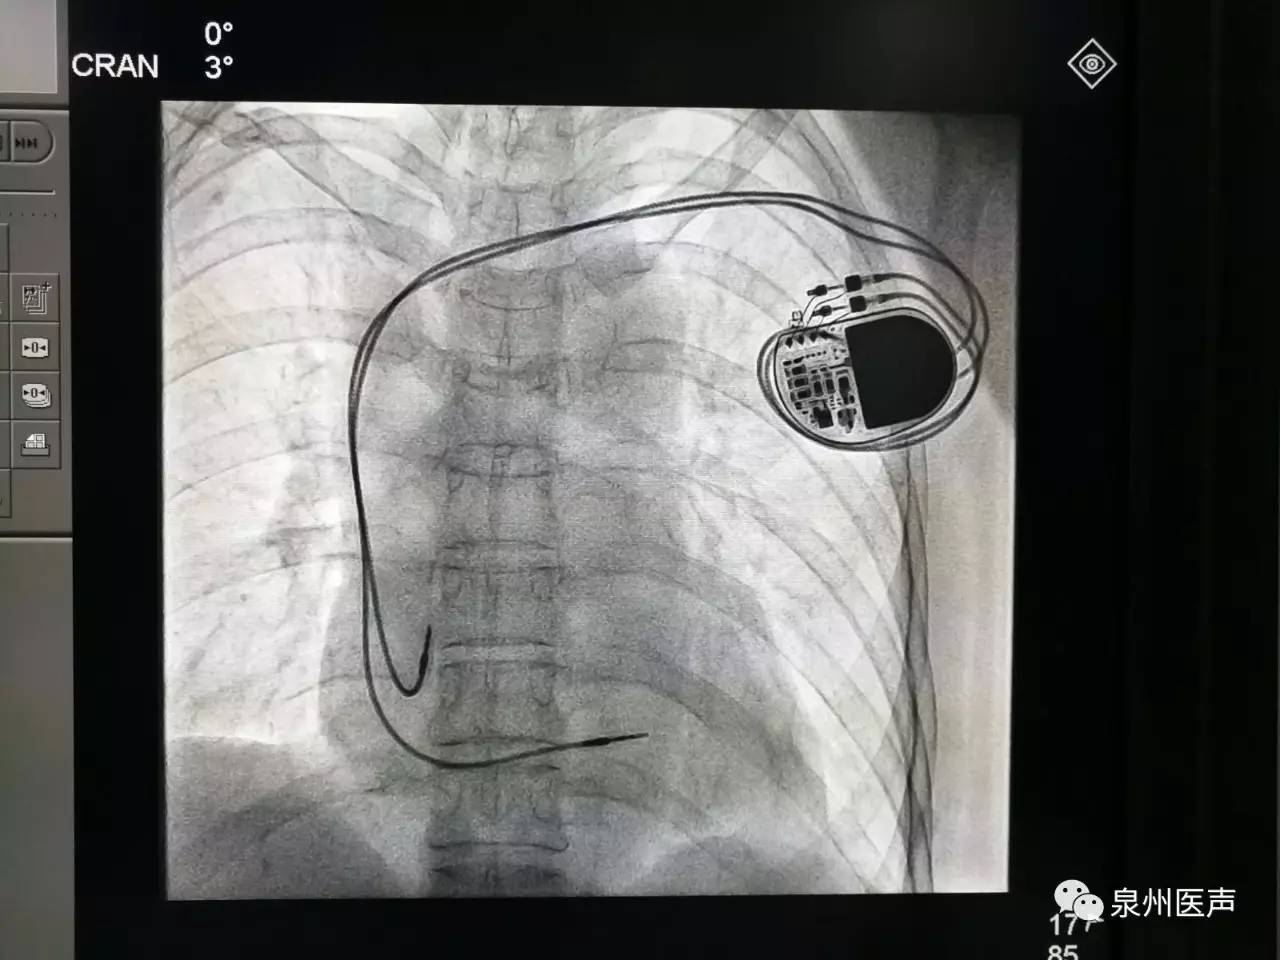

微創(chuàng)、樂普、先健填補(bǔ)國產(chǎn)起搏器市場空白,釋放哪些信號?

其他 2021-05-26

世界最小起搏器,正式進(jìn)入中國市場!

器械之家曾做過專題報(bào)道的“世界最小起搏器”(嬰兒用除外)在經(jīng)過了漫長的中國本土臨床研究后,終于獲得NMPA批準(zhǔn),正式于中國上市!